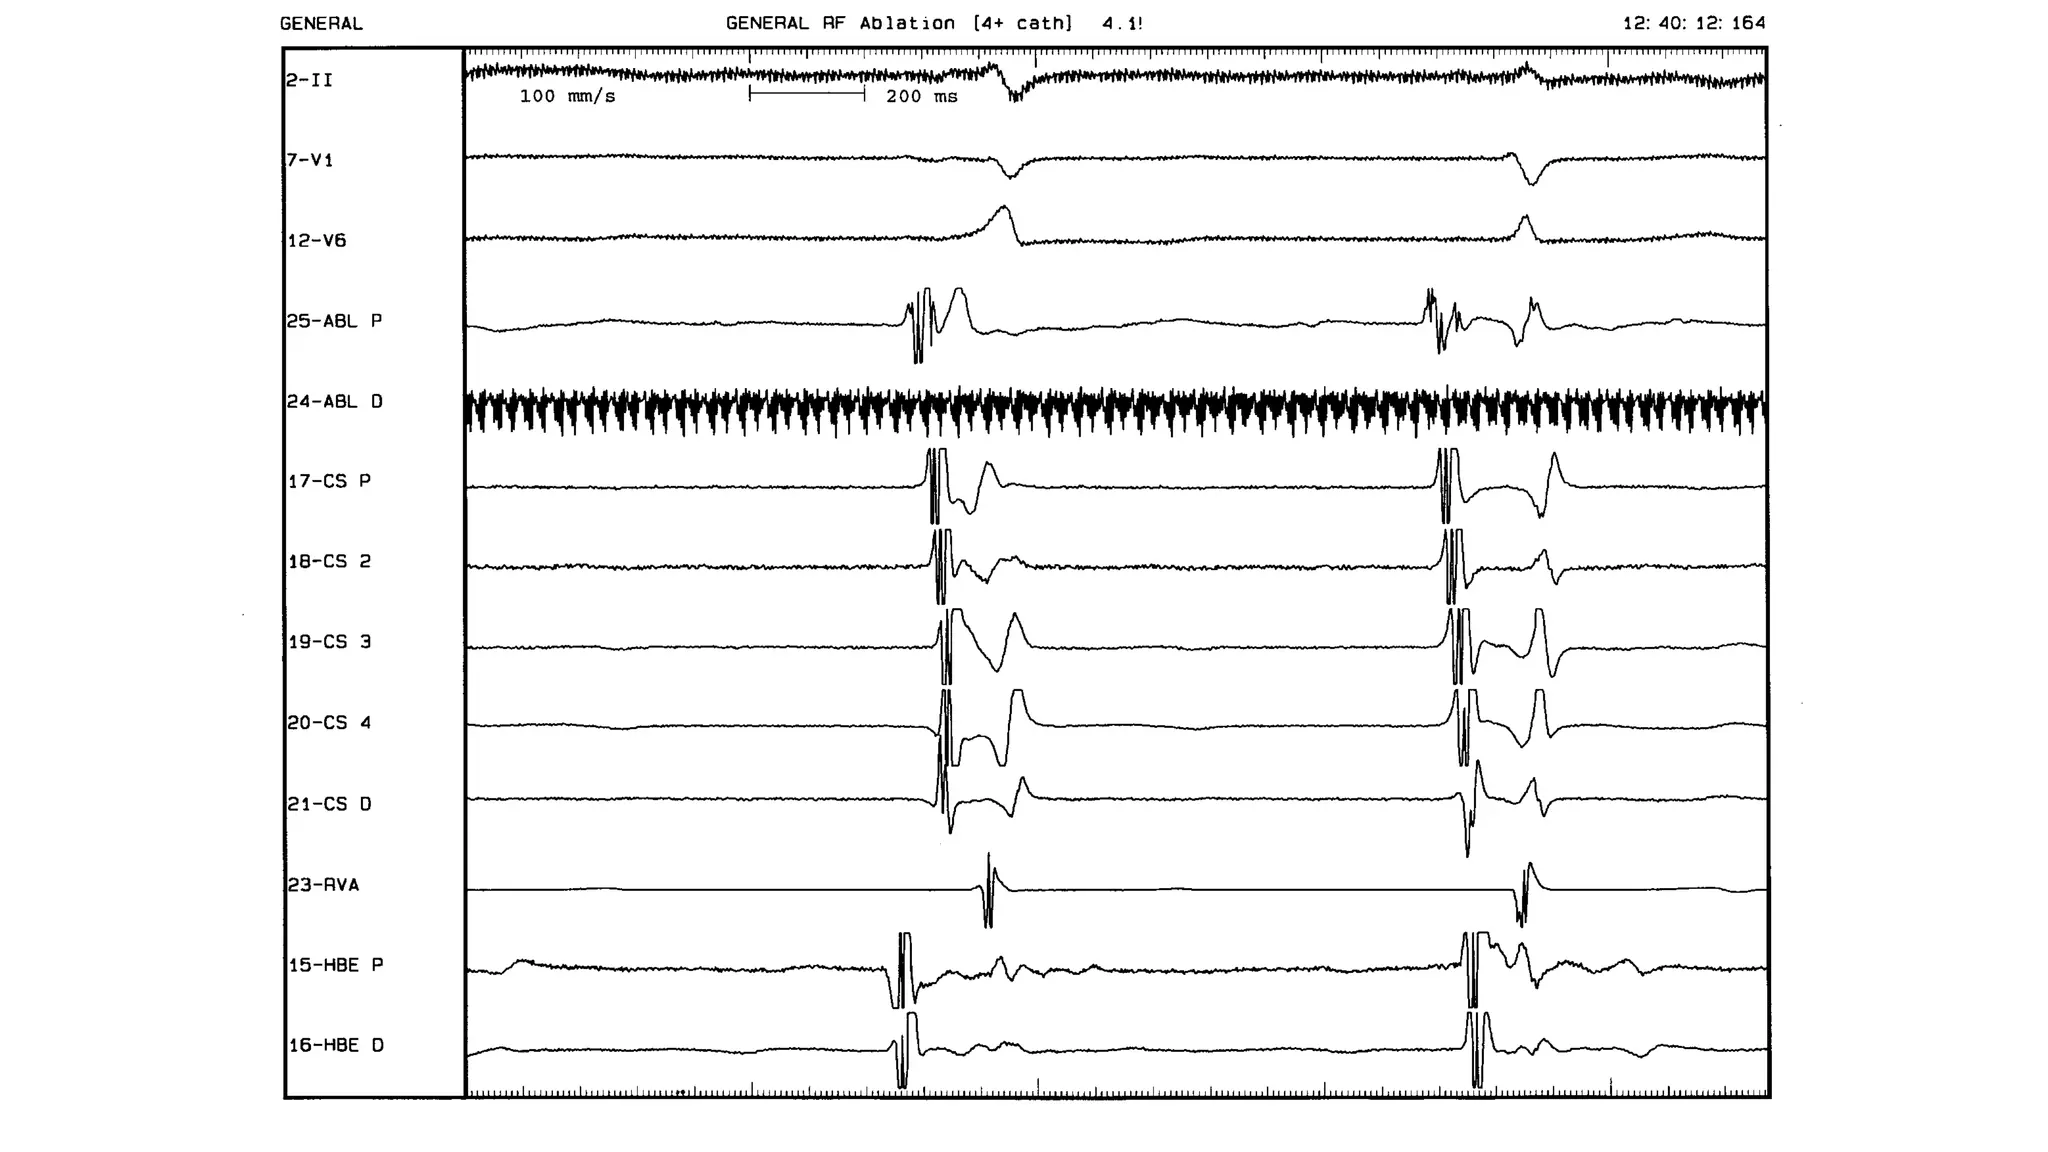

An electrophysiologic study involves inserting electrode catheters into the heart to record electrical activity and induce arrhythmias. The document discusses: 1. The procedure involves placing catheters in the heart to record electrograms from the atria, His bundle, ventricles and coronary sinus. 2. The aims are diagnostic to evaluate arrhythmias and bradycardias, and therapeutic for ablation of arrhythmias. 3. Key measurements taken include intervals between P waves, His bundle activation and QRS complex to identify conduction abnormalities. 4. Tracings are analyzed to determine the rhythm, sequence of activation, effects of pacing, and identify arrhythmia mechanisms like accessory pathways